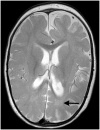

Migrating partial seizures of infancy, also known as epilepsy of infancy with migrating focal seizures, is a rare early infantile epileptic encephalopathy with poor prognosis, presenting with focal seizures in the first year of life. A national surveillance study was undertaken in conjunction with the British Paediatric Neurology Surveillance Unit to further define the clinical, pathological and molecular genetic features of this disorder. Fourteen children with migrating partial seizures of infancy were reported during the 2 year study period (estimated prevalence 0.11 per 100,000 children). The study has revealed that migrating partial seizures of infancy is associated with an expanded spectrum of clinical features (including severe gut dysmotility and a movement disorder) and electrographic features including hypsarrhythmia (associated with infantile spasms) and burst suppression. We also report novel brain imaging findings including delayed myelination with white matter hyperintensity on brain magnetic resonance imaging in one-third of the cohort, and decreased N-acetyl aspartate on magnetic resonance spectroscopy. Putaminal atrophy (on both magnetic resonance imaging and at post-mortem) was evident in one patient. Additional neuropathological findings included bilateral hippocampal gliosis and neuronal loss in two patients who had post-mortem examinations. Within this cohort, we identified two patients with mutations in the newly discovered KCNT1 gene. Comparative genomic hybridization array, SCN1A testing and genetic testing for other currently known early infantile epileptic encephalopathy genes (including PLCB1 and SLC25A22) was non-informative for the rest of the cohort.